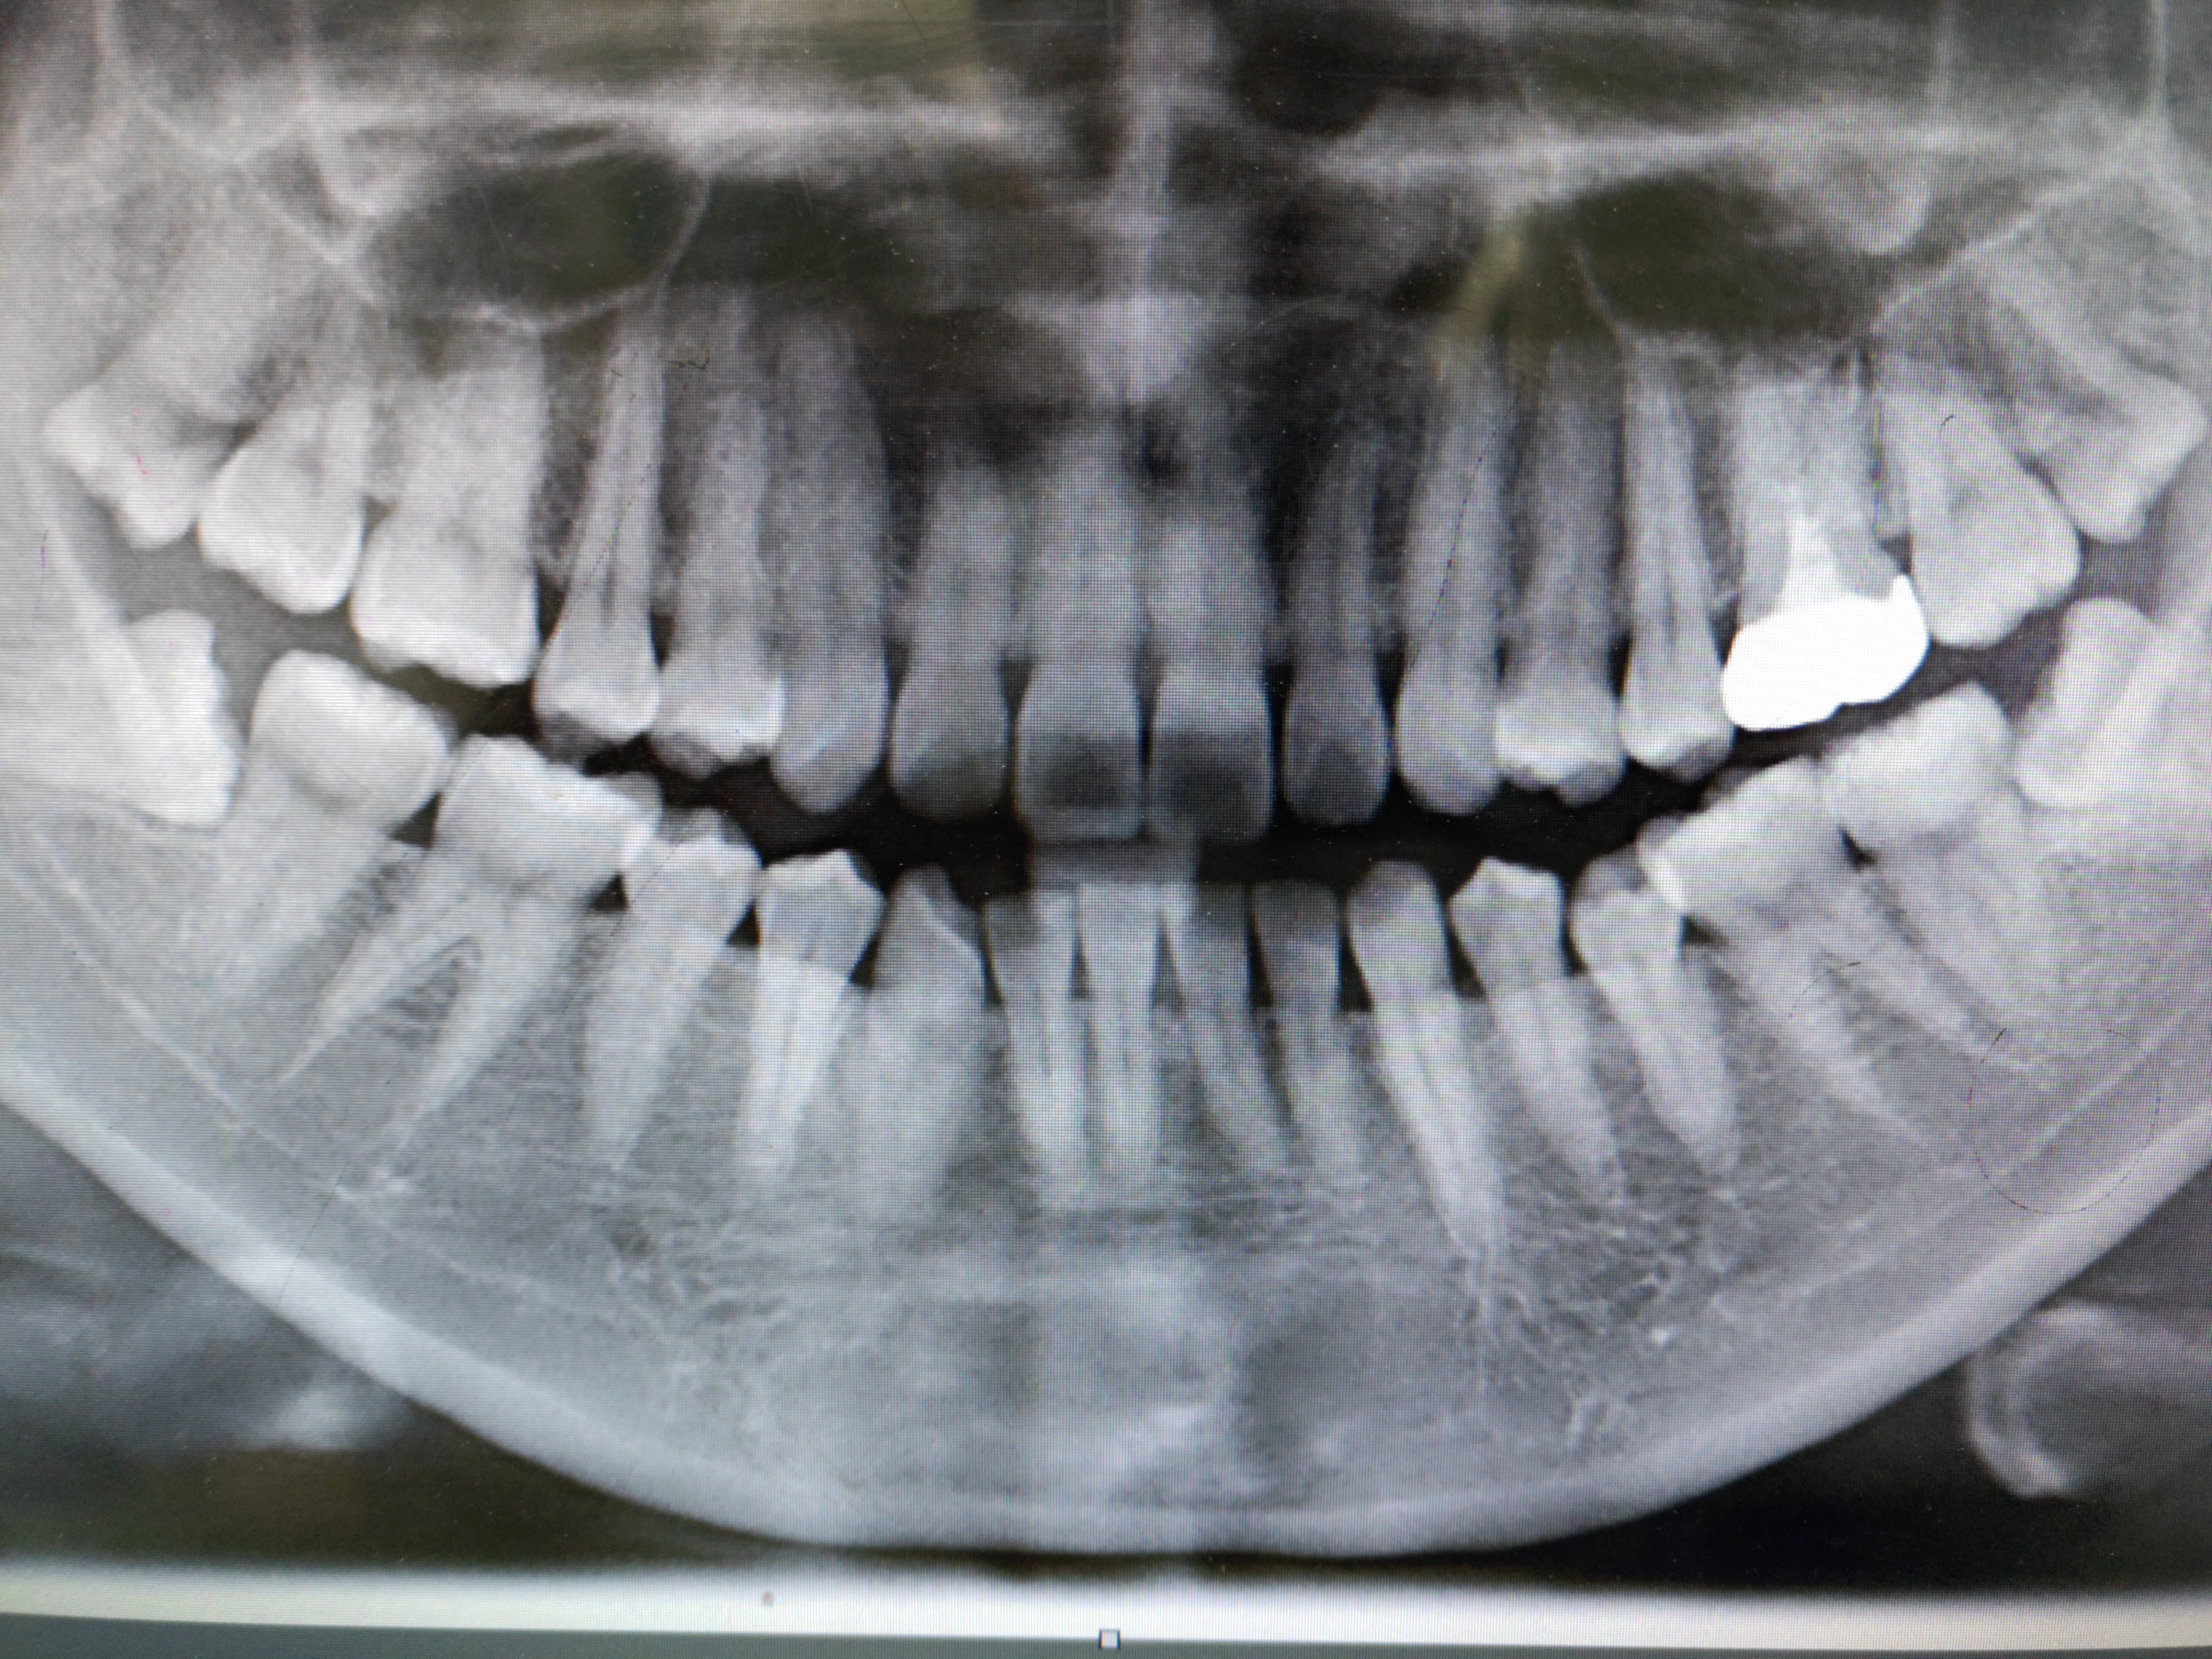

1.蛀牙:如果智齿蛀牙,除了很简单的咬合 智齿 面不深的蛀牙可以补之外,那些邻接面蛀牙,需要很好的技术,以及蛀得很深,甚至需要 根管治疗 的,我们一律建议拔除, 杜绝后患 。 2.侵犯邻牙:通常患者不自知,而由牙医以X光诊断得知。 通常智齿萌发的空间不足,而会倒在第二大臼齿上,因而造成第二大臼齿清洁不易,甚至是牙齿部分吸收的 现象 ,造成患者不10/5/21 · 由于智齿长在嘴里边,清洁起来较困难,因此即便是位置长的很正的智齿,也容易发生蛀牙现象。为避免累及其他牙齿,建议尽早拔掉智齿。 5、没有对咬的智齿 如果智齿对面没有相抗衡的智齿来对咬的话,智齿过度萌生就会影响咬合,导致对面牙龈肿痛。30/5/14 · 智齿拔除适应症有哪些: 1龋齿(蛀牙):如果智齿蛀牙,除了很简单的咬合面不深的蛀牙可以补之外,那些邻接面蛀牙,需要很好的技术,以及蛀得很深,甚至需要根管治疗的,我们一律建议拔除,杜绝后患。 2造成邻牙病变:通常患者不自知,而由牙医以x光诊断得知。

5/6/17 · 2、蛀牙 如果智齿蛀牙,除了很简单的咬合面不深的蛀牙可以补之外,那些邻接面蛀牙,需要很好的技术,以及蛀得很深,甚至需要根管治疗的,我们一律建议拔除,杜绝后患。 3 3、清洁不易 由于空间不足的关系,智齿常长得歪七扭八,因此常造成清洁牙齿的7/2/15 · 拔除智齿适应症: 1龋齿(蛀牙):如果智齿蛀牙,除了很简单的咬合面不深的蛀牙可以补之外,那些邻接面蛀牙,需要很好的技术,以及蛀得很深,甚至需要根管治疗的,我们一律建议拔除,杜绝后患。 2造成邻牙病变:通常患者不自知,而由牙医以x光诊断得知。/7/18 · 1蛀牙:如果智齿蛀牙,除了很简单的咬合面不深的蛀牙可以补之外,那些邻接面蛀牙,需要很好的技术,以及蛀得很深,甚至需要根管治疗的,我们一律建议拔除,杜绝后患。 2侵犯邻牙:通常患者不自知,而由牙医以X光诊断得知。 通常智齿萌发的空间不足,而会倒在第二大臼齿上,因而造成第二大臼齿清洁不易,甚至是牙齿部分吸收的现象,造成患者不舒适